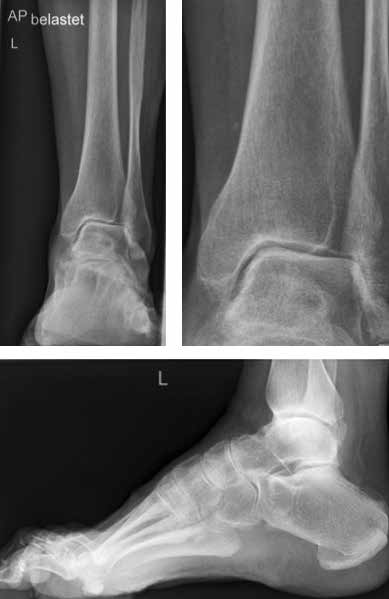

Arthrose stellt weltweit die häufigste Gelenkerkrankung dar und hat damit einen wesentlichen sozioökomischen Einfluss 1. Während 15 % der weltweiten erwachsenen Bevölkerung von Arthrose betroffen sind 2, leiden lediglich 1 % der Bevölkerung 3 bzw. 4,4 % der Arthrosepatienten 4 an einer Arthrose des oberen Sprunggelenks (OSG). Circa 80 % der Arthrosen des OSG sind ursächlich als posttraumatisch einzustufen, nur 9 % gelten als primäre Arthrosen. Dies unterscheidet die Arthrose des OSG von Coxarthrose (58 % primär) und Gonarthrose (67 % primär). 13 % treten im Rahmen systemischer Erkrankungen wie rheumatoider Arthritis, Hämochromatose, Hämophilie oder Osteonekrose auf 5 6. Die posttraumatische Arthrose des OSG wird besonders nach in Achsabweichung verheilten Frakturen (Pilon-tibiale-Frakturen, Weber-A‑, ‑B- und ‑C-Frakturen; Abb. 1a), Bandinstabilitäten des lateralen und medialen Bandapparates des OSG (Lig. fibulotalare anterius, Lig. fibulocalcaneare, Lig. fibulotibiale posterius etc.), nach rezidivierenden ligamentären Verletzungen sowie nach Gelenkverletzungen mit Knorpelschaden, „flake fractures“ oder „bone bruise“ beobachtet 7. Daher ist bei den vergleichsweise häufigen Weber-B- und ‑C-Frakturen die osteosynthetische Versorgung mittels Drittelrohrplatte und Zugschraube (Abb. 1b) sowie ggf. Syndesmosennaht mit Implantation einer Stellschraube mit millimetergenauer Reposition essentiell, um langfristig die Funktionsfähigkeit des OSG aufrechtzuerhalten und eine frühzeitige posttraumatische Arthrose zu verhindern 8.

Das besondere Merkmal der Arthrose des OSG ist das relativ junge Alter der Patienten im Vergleich zur Arthrose anderer Gelenke der unteren Extremität, da die meistens zugrunde liegenden Traumata Sportunfälle sind. Zusätzlich werden ein schnellerer Funktionsverlust des Gelenks und eine beschleunigte Progression der Erkrankung bis zum Erreichen des Endstadiums (innerhalb von 10 bis 20 Jahren) beobachtet 9 (Abb. 2a). Negativ beeinflussende Faktoren für die Entwicklung einer Arthrose des OSG sind: Achsfehlstellungen oder angeborene Deformitäten der unteren Extremität, Muskeldysbalance 10, angeborene oder erworbene ligamentäre Fehlentwicklungen, Alter, Geschlecht und genetische Prädisposition 11.

Primäres radiologisches Verfahren ist die konventionelle Röntgendiagnostik des oberen Sprunggelenkes unter Belastung mit dem eigenen Körpergewicht. Hierbei können bereits unterschiedlich stark ausgeprägte Gelenkdestruktionen diagnostiziert werden. Neben der Gelenkspaltverschmälerung können Osteophytenbildung und subchondrale Sklerosierung sowie Zystenbildung erhoben werden. Die Klassifikation nach Morrey/Wiedemann basiert auf diesen radiologischen Befunden 19: